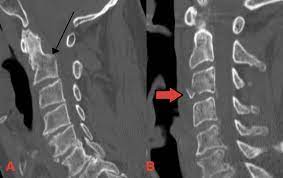

- Bony injury: Vertebral body, pedicle, lamina, spinous/transverse process fractures.

- Alignment: Step-offs, listhesis, abnormal angulation, loss of normal lordosis.

- Soft tissues: Prevertebral soft tissue swelling, ligamentous injury, haematoma.

| C-spine fractures | Fracture lines of vertebral bodies or posterior elements, possible malalignment. Look carefully at occipito-cervical and cervico-thoracic junctions. |